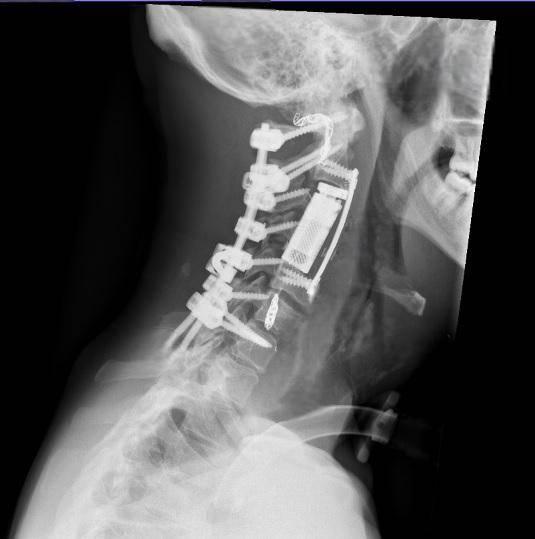

اشتملت المرحلة الجراحية على تثبيت خلفي للعمود الفقري من الفقرة العنقية الأولى حتى السابعة مع تحرير النخاع الشوكي وتأمين استقرار الفقرات قبل إجراء استئصال كامل للورم والفقرات المصابة بطريقة الاستئصال الكامل في كتلة واحدة عبر المدخل الأمامي، تلاه تعويض الفقرات باستخدام قفص فقري تمديدي مع تثبيت أمامي لضمان الثبات الكامل للعمود الفقري.